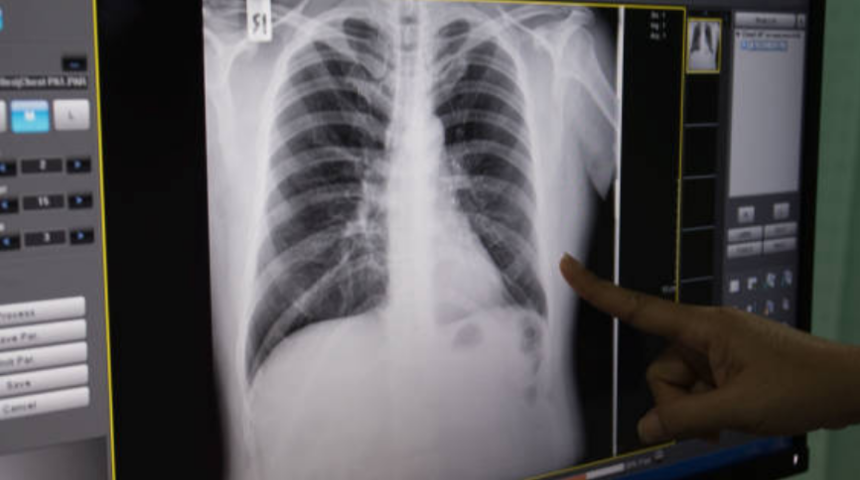

Kronik Obstrüktif Akciğer Hastalığı, yani bilinen adıyla KOAH, akciğerlerdeki hava yollarının daralmasına bağlı olarak, nefes alıp verme sırasında hava akımının kısıtlanması ile karakterize bir hastalık. KOAH’ın toplumda oldukça yaygın olduğunu ancak buna rağmen yeterince bilinmediğinin altını çizen Anadolu Sağlık Merkezi Göğüs Hastalıkları Uzmanları Prof. Dr. Kemal Tahaoğlu ve Dr. Esra Sönmez, “Kişiyi zamanla başkalarının desteğine bağımlı hale getirmesi, kalıcı işgücü kayıplarına neden olması KOAH’ı, toplumsal anlamda da ciddiye alınması gereken bir soruna dönüştürüyor” dedi. Sigara dumanına maruz kalan çocukların akciğer hastası olma olasılığının 2 ile 3 kat arttığını belirten Prof. Tahaoğlu ve Dr. Sönmez, “Bu nedenle, ebeveynlerin bu konuda gerekli hassasiyeti göstermeleri ve çocukların yanında sigara içmemeleri hayati öneme sahip” uyarısında bulundu.

Hastalığın önemli bir kısmının özellikle erken dönemlerde görülen bazı şikayetlerle kendini gösterdiğine dikkat çeken Prof. Dr. Kemal Tahaoğlu ve Dr. Esra Sönmez, “KOAH, ileri evresinde nefes darlığı, öksürük, balgam çıkarma, göğüste tıkanma, hırıltılı solunum ve morarma gibi yakınmalara yol açıyor. Bu şikayetler sinsice başlayıp, aylarca, hatta yıllarca devam edebiliyor. Ancak hastaların önemli bir kısmında, özellikle erken dönemde belirtisiz olabilmesi ya da başka hastalıklarla da örtüşen bazı şikayetlerin oluşması tanıyı geciktiren bir etken oluyor” şeklinde konuştu.KOAH’ın belirtilerini sıralayan Prof. Tahaoğlu ve Dr. Sönmez,şunları söyledi: